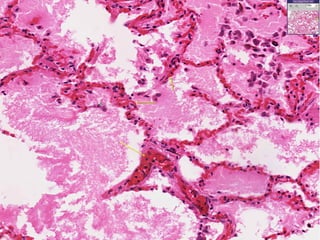

CVC Lungs Micro:- Rupture ofcongested vessel results in edema & hemorrhage. The alveolar septa appears thickened and fibrotic. The alveoli are dilated and contain edema fluid and RBC’s and macrophages. Lysis of RBC’s releases hemosiderin pigment which is taken up by macrophages in the alveoli – HEART FAILURE CELLS.

• #18 View of pulmonary congestion and edema. Often caused by an increase in hydrostatic pressure, a protein poor transudate seeps into interstitial and alveolar spaces. Note the engorged alveolar wall capillaries. If capillaries rupture, RBCs will escape into the alveolar space

• #19 Heart failure cells are hemosiderin laden macrophages. Blood escapes into the alveolar space because chronic congestion causes the thin walled alveolar capillaries to burst. Note the thickening of the alveolar septae. This is caused by chronic pulmonary congestion and edema. Note the thickening of the alveolar septae. This is caused by chronic pulmonary congestion and edema.